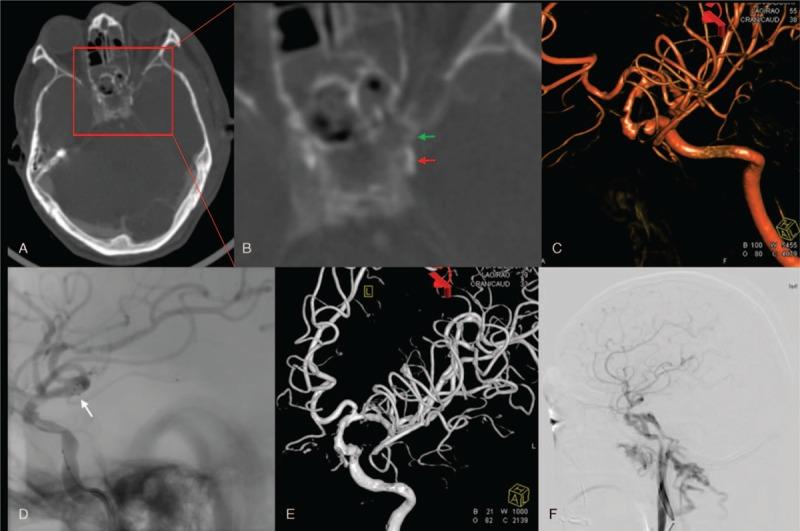

Here we report on 3 BICI cases that demonstrated optic nerve injuries after craniofacial injuries. All 3 patients showed post-trauma vision loss on the injured side.

Optical canal fractures can be found in these patients, and carotid sulcus was compressed by the fragments. Computed tomography angiography (CTA) and digital subtraction angiography (DSA) were performed in all 3 patients.

Case 1 was given no further treatment, except for symptomatic support and rehabilitation therapy. Case 2 was treated with antiplatelet therapy for 3 days, and then a stent was inserted in the injured internal carotid. Case 3 received antiplatelet therapy and a internal carotid compression test was performed simultaneously for 2 weeks, then the injured internal carotid was completely blocked.

Case 1 developed cerebral infarction that resulted in unilateral hemiplegia. Due to timely treatment, the remaining 2 patients had a better prognosis.

这些患者可见视神经管骨折,骨折碎片压迫颈动脉沟。所有3例患者均进行了计算机断层扫描血管造影(CTA)和数字减影血管造影(DSA)。

病例1除给予对症支持和康复治疗外,未进行进一步治疗。病例2接受了3天的抗血小板治疗,然后在受伤的颈内动脉置入支架。病例3接受抗血小板治疗并同时进行颈内动脉压迫试验2周,然后完全闭塞受伤的颈内动脉。

病例1发生脑梗死,导致单侧偏瘫。由于治疗及时,其余2例患者预后较好。